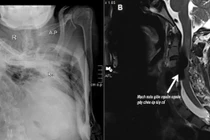

Hình ảnh cột sống của bệnh nhân trên phim chụp - Ảnh BVCC

Bệnh nhân nhập viện với chẩn đoán sỏi niệu quản trái 1/3 giữa và 1/3 trên, theo dõi nhiễm khuẩn niệu, viêm cột sống dính khớp, nang thận phải, sỏi thận trái. Cột sống bị dính cứng khiến khe gian đốt hẹp, việc chọc kim tủy sống trở nên vô cùng phức tạp.

Dù chỉ còn một khe rất nhỏ – tức cánh cửa rất hẹp – nhưng bằng sự nhạy cảm nghề nghiệp, bác sĩ Lê Xuân Hùng đã khéo léo vượt qua, tránh được một cuộc gây mê có thể gặp nhiều khó khăn và rủi ro.